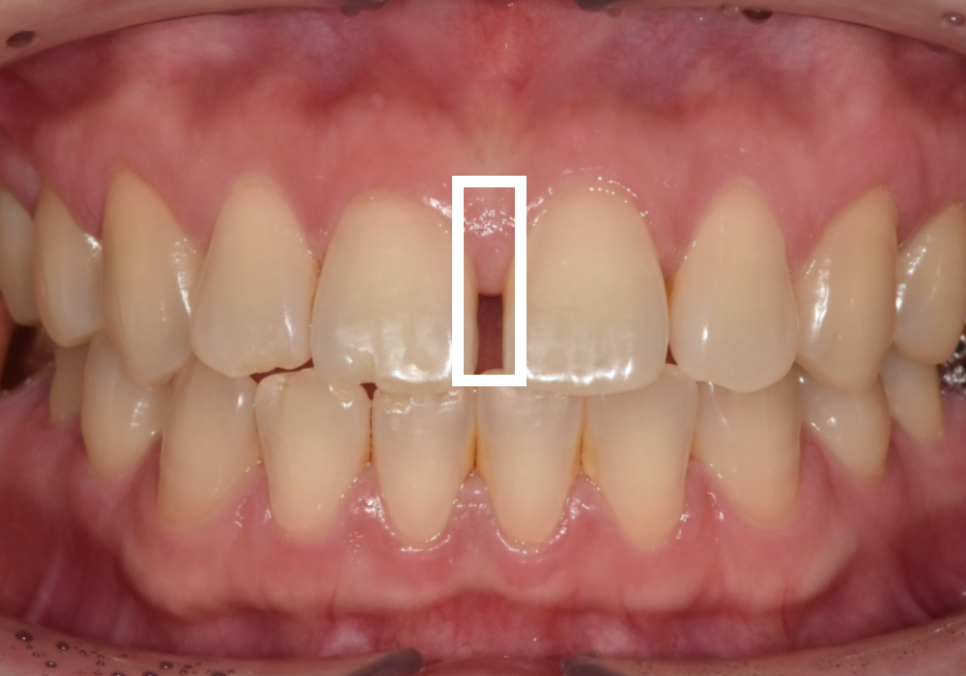

얼마 전 저희 치과를 찾으신 환자분은

가운데 앞니가 벌어진 상태였고,

동시에 왼쪽 위 어금니(#26)도

상실된 상태였어요.

이 환자분의 가장 큰 고민은

'치료 기간'이었는데요~

만약 교정을 선택한다면

1~2년의 교정 기간이 모두 끝난 뒤에야

임플란트를 할 수가 있어요.

임플란트는 한 번 뼈에 고정되면

이동이 힘들기 때문인데요.

환자분 입장에서 교정은

치료 기간이 너~무 길어져서

부담을 느낄 수밖에 없는 상황....

결국 환자분과 충분한 상의 끝에,

앞니 4개는 라미네이트로 빠르게 개선하고,

어금니는 즉시 임플란트를

진행하기로 결정했답니다.